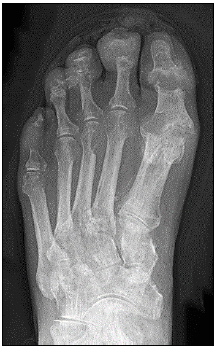

“Homem, 43 anos, refere dor, edema e calor em região das articulações dos dedos e mãos à direita, associadas à dor em região do hálux esquerdo, desencadeada após ingestão alcoólica. Realizou a radiografia, conforme a imagem a seguir.”

Qual o tratamento mais recomendado nesse caso?